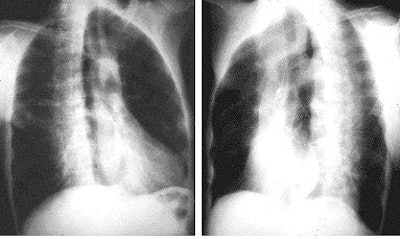

A case of subpulmonic effusion (pleural effusion located between the lung and the diaphragm). Subpulmonic effusions are suspected by hemidiaphragm elevation. In this case, a lateral decubitus x-ray with the patient lying on the side of the effusion is helpful not only to ensure the presence of effusion but also to quantify the volume. Image courtesy of Dr. Naveed Ahmad.